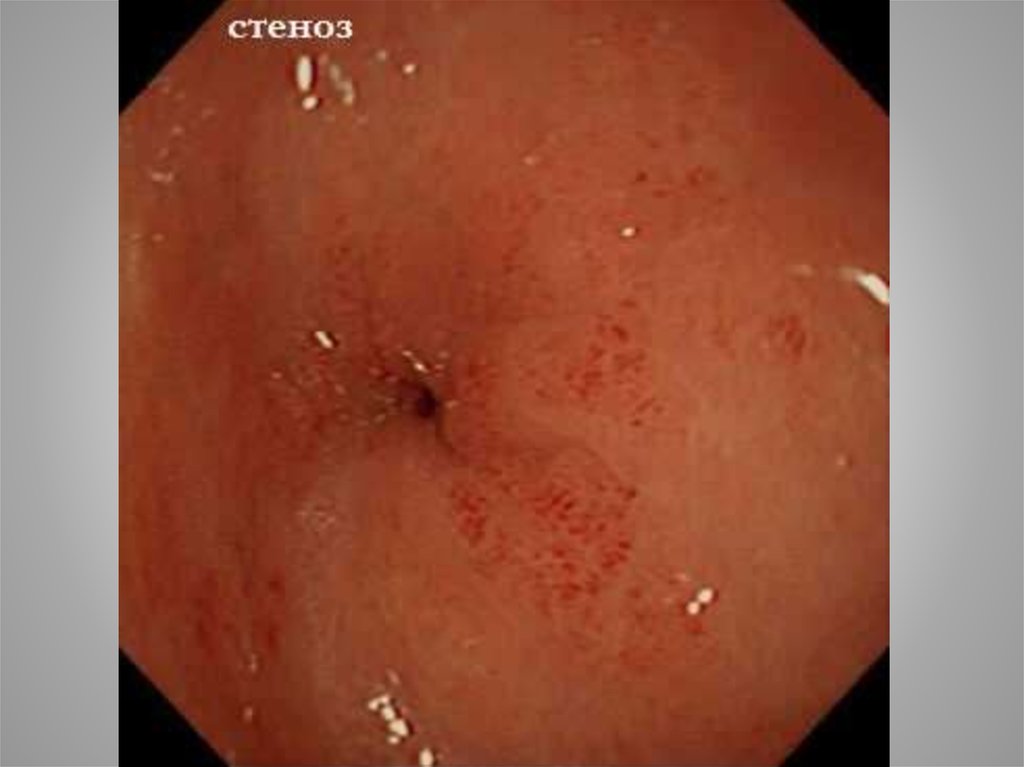

49. Рубцовый стеноз и деформации

Рубцы образуются в местах, где

язва заживает, рубцуется, либо

окружающие рубцовые ткани

создают деформации («песочные часы»). Нередко это происходит в местах сужения, чаще

всего в области пилорического

жома.

50. Рубцовый стеноз и деформации

Клиника стеноза желудка складывается из следующих 5 компонентов:

1) рвота;

2) размеры желудка;

3) тонус желудка;

4) интенсивность эвакуации бария по

рентгеновским данным, проходимость

по данным эндоскопии;

5) биохимические нарушения

51.

3 вида рвоты: на

высоте болей;

при стенозе;

при кровотечении

52.

Срочно сделать

анализы крови и

мочи?

Что еще?

53.

В ОРИТ проведена инфузионная терапия (состав?). Зондом эвакуировано около 3 л содержимого

с примесью пищи. Зонд

оставлен на сутки. Судороги прекратились.

54. Компенсированный стеноз

Отмечается лишь по эндоскопическим данным,

когда провести эндоскоп в ДПК не удается

рвоты нет или она редкая;

размеры желудка нормальные;

тонус сохранен

барий покидает желудок в срок

менее 6 часов;

биохимических расстройств нет

Желательно оперировать больных именно в

этой стадии.